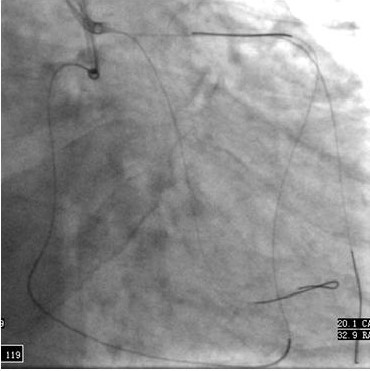

在2008年的CTO峰会上,笔者报道了该技术,还不是太成熟,在此简单介绍一下。当逆向钢丝进入近端真腔或接近正向指引导管时,用抓捕器将逆向钢丝经指引导管拉出体外,然后用钢丝的头端做尾端进行介入治疗,但是,在钢丝外拉过程中,由于收缩期钢丝被心肌“咬住”,只能在心脏舒张期缓慢外拉,通常钢丝头端会被拉折,然而,抓捕器在指引导管中很难再次捕获被拉折的钢丝,这时,可以通过正向较大(3.0或3.5 mm)将钢丝铆紧捕获,然后在体外用抓捕器将指引导管导回,完成介入治疗(图2)。目前的导引钢丝长度受限不足以双侧暴露于体外,使介入治疗完成后导丝回撤会有一定困难,可以一侧用微导管,另一侧用单轨球囊对接,在心脏舒张期取出导引钢丝。